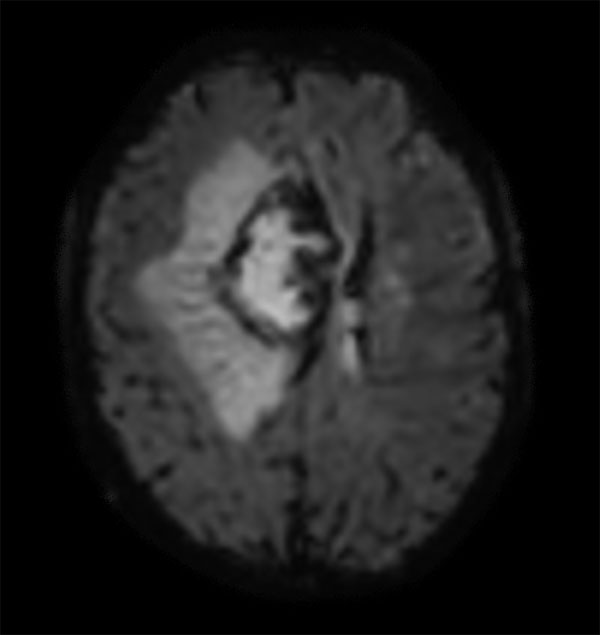

Advanced Neuro imaging - pCASL

Clinique Saint Joseph Imagerie Medicale, Liege, Belgium